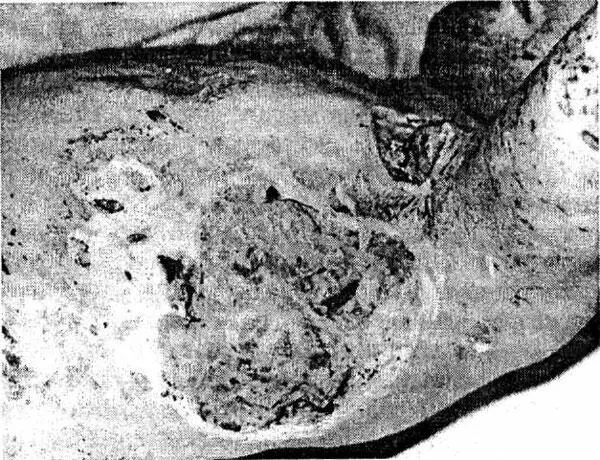

Отмечается следующая последовательность процессов заживления гнойных ран. Вначале происходит очищение очага воспаления от всех некротизированных клеток, тканей, сгустков крови и т. д. После этого на отдельных участках стенок гнойной полости появляются разрастания клеток в виде красных узелков, которые, постепенно увеличиваясь в количестве и размерах, покрывают все стенки и дно раны. Эти красные узелки состоят из молодых соединительных клеток (фибробластов) и называются грануляционной тканью, которая заполняет всю полость гнойного очага до поверхности кожи (рис. 1). После этого кожный эпителий, разрастаясь, покрывает грануляции, клетки которой (фибробласты) постепенно образуют волокнистую соединительную ткань – так образуется рубец.

Рис 1 Обширные гранулирующие раны грудной клетки Макроскопически при - фото 1

Рис. 1. Обширные гранулирующие раны грудной клетки

Макроскопически при заживлении вторичным натяжением происходят следующие процессы. В отличие от первичного заживления, когда капилляры кровеносных сосудов одной стенки раны соединяются с капиллярами другой стенки, при вторичном заживлении при наличии значительной раневой полости, капилляры, разрастаясь, не достигают противоположной стенки раны, а образуют петли.